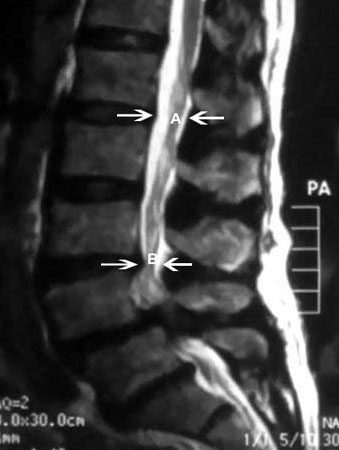

პაციენტებს შესაძლოა აღენიშნოთ ზურგის ტკივილი, რომელიც ხშირად ნეიროგენულია და მეორეულად განვითარებული წელის მალების ნერვთა ფესვების მექანიკური შევიწროებით.[19][Figure caption and citation for the preceding image starts]: სპინალური სტენოზის მაგნიტურ-რეზონანსული გამოკვლევა: (A) შემოსაზღვრავს სპინალური არხის ნორმალურ საგიტალურ დიამეტრს. (B) შემოსაზღვრავს სპინალური არხის მძიმე შევიწროვებასექიმ Dr K. Singh საკუთრება; გამოყენებულია ნებართვით [Citation ends].

[Figure caption and citation for the preceding image starts]: ხერხემლის სტენოზის MRI: ისრებით მითითებულია ხერხემლის არხის საშუალო ფორმის სტენოზი. ის გამოწვეულია ფასეტური სახსრისა და ყვითელი იოგების ჰიპერტროფიითექიმ Dr K. Singh საკუთრება; გამოყენებულია ნებართვით [Citation ends].